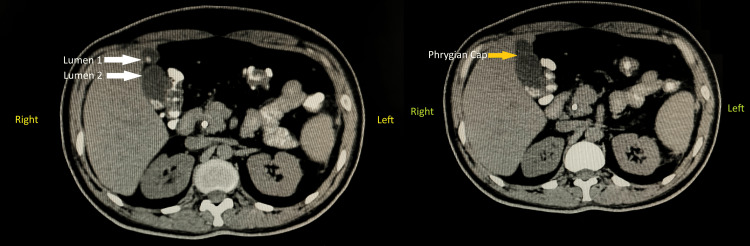

Once the reconstruction was complete, the incisions were meticulously closed in layers to promote proper healing, and a drain was inserted to prevent fluid accumulation in the abdominal cavity, ensuring optimal postoperative recovery. Postoperative surveillance for dehiscence or fistula involved monitoring the surgical site and the patient’s overall condition to detect any signs of complications, including visual inspection of the incision site for redness, swelling, or discharge, and gentle palpation for tenderness and abnormal tissue characteristics. Additionally, the patient was asked about any symptoms experienced, such as increased pain or fever. Throughout the procedure, utmost care and precision were exercised to minimise complications and maximise the patient’s chances of a successful outcome. Additionally, the incidental finding of the Phrygian cap of the gallbladder was noted and managed appropriately within the context of the overall surgical plan. This anatomical variant was meticulously removed along with the primary focus of the surgery. The Phrygian cap of the gallbladder is shown in Figure 1. Computed tomography showing the abnormal gallbladder and Phrygian cap is represented in Figure 2.

The incidental discovery of a Phrygian cap of the gallbladder during a Whipple’s procedure for pancreatic head cancer in a 48-year-old female presents a unique and noteworthy finding. The Phrygian cap anomaly, characterised by a fold or hooding of the gallbladder fundus over the body, is a rare congenital variation often detected incidentally during imaging or surgical procedures [ref. 8]. In this case, the discovery of the Phrygian cap adds a layer of complexity to an already intricate surgical intervention for pancreatic head cancer. The presence of a Phrygian cap may alter the usual anatomical landmarks, requiring adaptability and precision to avoid accidental injury to the gallbladder or bile ducts [ref. 5].

In the case of a 65-year-old female reported by Kulkarni et al., the Phrygian cap of the gallbladder was discovered during an emergency exploratory laparotomy undertaken for a sealed-off perforation at the pyloric part of the stomach [ref. 9]. In our case of a 48-year-old female, it was incidentally noted during a Whipple’s procedure performed for pancreatic head cancer. Both cases involve the identification of a gallbladder anomaly during surgical intervention for other conditions. However, the approach to managing the gallbladder anomaly differs significantly between the two cases [ref. 9]. In our case, where the patient underwent a Whipple’s procedure, the Phrygian cap was meticulously removed along with the primary focus of the surgery, namely pancreatic head cancer. This approach aligns with the principle of comprehensive surgical intervention aimed at addressing all identifiable pathologies within the operative field.

The case report details the management of obstructive jaundice and pancreatic head cancer in a 48-year-old female, complicated by the incidental discovery of a Phrygian cap of the gallbladder during Whipple’s procedure. The treatment involved CBD stenting for jaundice and Whipple’s surgery for cancer, with meticulous attention to the incidental findings. Surgical adaptability and careful decision-making were crucial, highlighting the importance of addressing primary and incidental pathologies for optimal patient outcomes. Postoperative monitoring and patient-centred care were emphasised. The case underscores the complexity of surgical interventions and the significance of thorough management in achieving favourable clinical results.